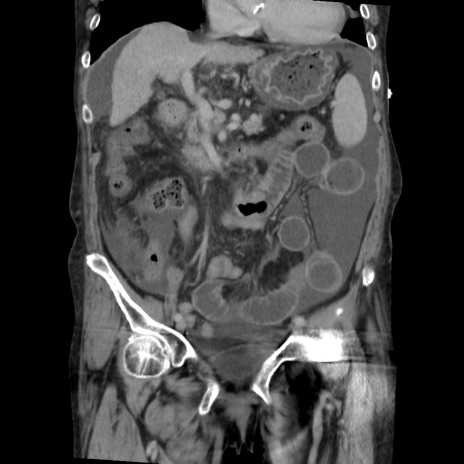

症例31(冠状断像)

【症例】80歳代 女性

【主訴】腹部膨満感

【現病歴】他院にて肝硬変にてフォロー中。1週間前から便秘、腹部膨満感、臍部腫瘤あり受診となる。

【既往歴】肝硬変

【身体所見】腹部膨隆あり、皮膚変化なし、疼痛なし。

【データ】WBC 4600、CRP 0.25